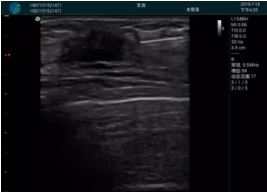

M20查看:囊內(nèi)回聲均勻,邊界清晰,囊壁光滑

M20引導(dǎo)抽吸術(shù)后囊腫消失,原區(qū)域空腔形成,脂肪層與腺體層架構(gòu)發(fā)生改變